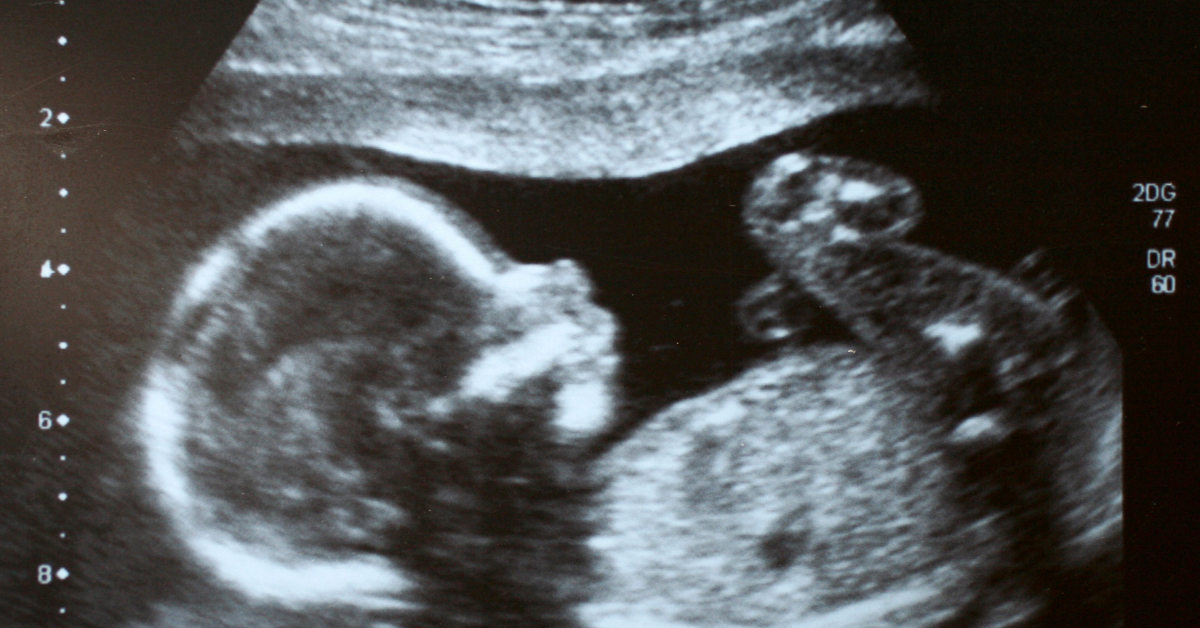

1. Ultrasonido.

Se utiliza para evaluar el crecimiento y desarrollo del bebé. Dependiendo del trimestre, puede detectar alteraciones estructurales, como malformaciones en el corazón, la columna vertebral o faciales (labio-paladar hendido). También detecta datos sugestivos de síndromes genéticos (Síndrome de Down o Turner). Lo realizan los gineco-obstetras o especialistas en medicina materno-fetal.